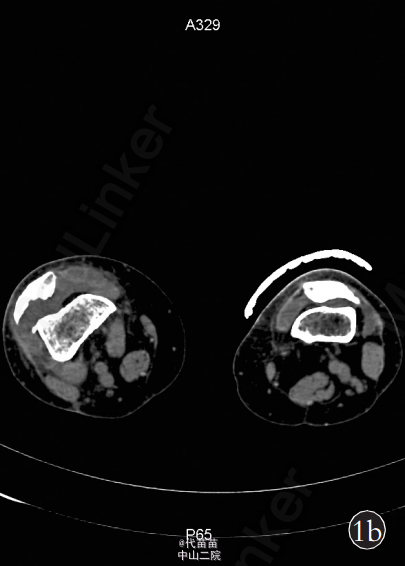

患者,女,70岁 。主因右膝关节间断性疼痛4年,加重2个月入院。患者自诉4年前无明显诱因出现膝关节间断性疼痛,活动时疼痛加重,休息后症状缓解,同时伴有右膝关节肿胀,膝关节活动时弹响症状明显,无夜间痛,未系统治疗。近2个月来患者疼痛症状逐渐加重,不能完全蹲下,并出现右小腿轻度肿胀。患者既往体健。查体:右膝关节肿胀,无发红及包块。右膝关节间隙按压痛阳性,浮髌试验阳性,髌骨摩擦试验阳性,右膝关节活动度:0°~130°,右下肢肌力Ⅳ级,其他检查未见异常。 影像学检查:X 线片示右侧膝关节不对称性变窄,关节面硬化,边缘可见唇样骨质增生,股骨下端凹槽样改变,边界较清楚,无骨膜反应,髌骨呈槽沟样改变(图 1a)。 右膝关节 CT 示右侧髌骨较薄,髌骨关节面锯齿样改变(图 1b)。MRI检查示膝关节腔内液体增多髌上囊内可见低信号影(图 1c)。为排除肿瘤及感染的可能性,进一步行实验室检查:血常规、ESR、CRP 及碱性磷酸酶以及 ECG 检查均未见异常。完善相关检查后, 择期行全膝关节表面置换术及滑膜清理术。为防止术后股骨缺损处出现病理性骨折,考虑选用制定型膝关节假体(股骨假体柄加长)。术中见:膝关节髌上囊内有大量陈旧性积血(图 1d),滑膜增生肥厚,股骨远端髁部上段可见轮廓清楚的凹陷性骨侵蚀面,股骨及胫骨骨赘形成,股骨髁及胫骨平台关节面软骨破坏,股骨外侧髁破坏严重,部分软骨下骨外露, 髌骨外侧变薄, 髌骨关节面有沟槽样凸凹不平(图1d),软骨面破坏,外侧较重,软骨下骨外露。 术中将病变关节囊及滑膜送检病理,快速病理回报:色素绒毛结节性滑膜炎可能性大。 术中彻底切除髌上囊、滑膜、髌下脂肪垫及半月板,切除胫骨表面、前十字韧带及后十字韧带,处理股骨髁,矫正 FTA 角为外翻 5°,安装 Depuy 公司 2 号股骨假体加长柄及2 号胫骨假体,胫骨假体上安装 8 mm 垫片,复位关节。检查内外侧软组织平衡良好,功能活动良好,此时行髌骨成形术,修理髌骨后见髌骨活动轨迹差, 缝合前向关节腔内软组织注入镇痛药物。 术后右侧膝关节侧位片示:假体固定位置良好,股骨加长柄通过股骨皮质缺损区(图 1e)。 术后病理诊断:色素绒毛结节性滑膜炎(图 1f)。 术后 24 h 拔除负压引流,伸直位